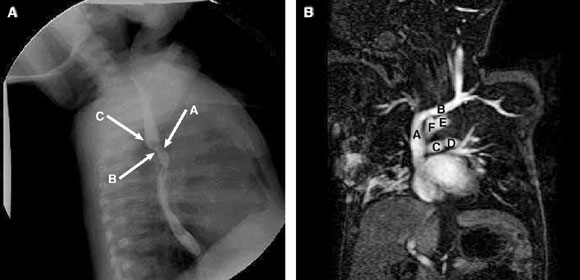

2: Investigations for biphasic stridor (Patient 2)

2A: Barium swallow, showing anterior (arrow A) and posterior (arrow B) compression of the oesophagus, together with a posterior bulge (arrow C) caused by a double aortic arch.

2B: Magnetic resonance image, showing the double aortic arch — superior vena cava (A), brachiocephalic vein (B), pulmonary arteries (C, D), prominent left aortic arch (E), and smaller right aortic arch (F).

A CXR showed a left, normally sited aortic arch and poor delineation of the distal tracheal air column suggestive of tracheomalacia. A barium swallow (Box 2A) showed significant oesophageal compression anteriorly and posteriorly, consistent with a double aortic arch. A magnetic resonance angiogram (Box 2B) confirmed the presence of the double aortic arch, as well as extrinsic, anterior compression of the distal trachea. Bronchoscopy, performed before surgery to divide the vascular ring, showed mild tracheomalacia.

The formation of the ring depends on the preservation or deletion of specific segments of the rudimentary aortic arch complex, or the presence of major arteries with anomalous origins or remnants (eg, ligamentum arteriosum) compressing the trachea and oesophagus. The double aortic arch is the most common form of vascular ring,4 and is characterised by persistence of both embryonic aortic arches, with separate carotid and subclavian arteries originating from each arch. The ascending aorta bifurcates anterior to the trachea to form the aortic arches, and each courses either right or left of the trachea and the oesophagus. The larger of the two arches usually crosses posterior to the oesophagus and unites with the other arch in the posterior mediastinum to form the single descending aorta. This can be seen as a posterior indentation on the mid-oesophagus on a barium swallow (Box 2A).